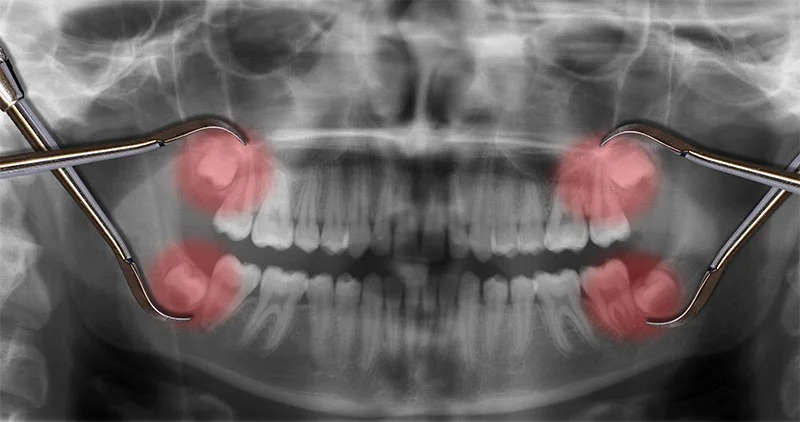

Phim pano và CBCT là nền tảng: pano ghi nhận toàn cảnh 2 hàm – xoang – khớp, còn CBCT (cắt lớp chùm tia hình nón) cho phép đo 3D khoảng cách chân răng với ống thần kinh/ xoang, giúp giảm thiểu rủi ro thần kinh – mạch – xoang và chọn kỹ thuật ít xâm lấn.

Vì sao có tê? Răng khôn hàm dưới có chân răng gần ống thần kinh răng dưới – một “đường cao tốc” chứa dây thần kinh và mạch máu chạy trong xương hàm; mở xương, chia chân răng hoặc phù nề quanh ống có thể gây chèn ép tạm thời. Mặt lưỡi hàm dưới gần dây thần kinh lưỡi, đôi khi dụng cụ – đường rạch kích thích gây tê nhẹ rồi tự hết. Những trường hợp chân răng “chồng” lên ống thần kinh trên phim CBCT sẽ được chúng tôi chọn kỹ thuật ít xâm lấn hơn, cân nhắc tách men thân răng trước, hoặc mổ chia nhỏ để an toàn tối đa.